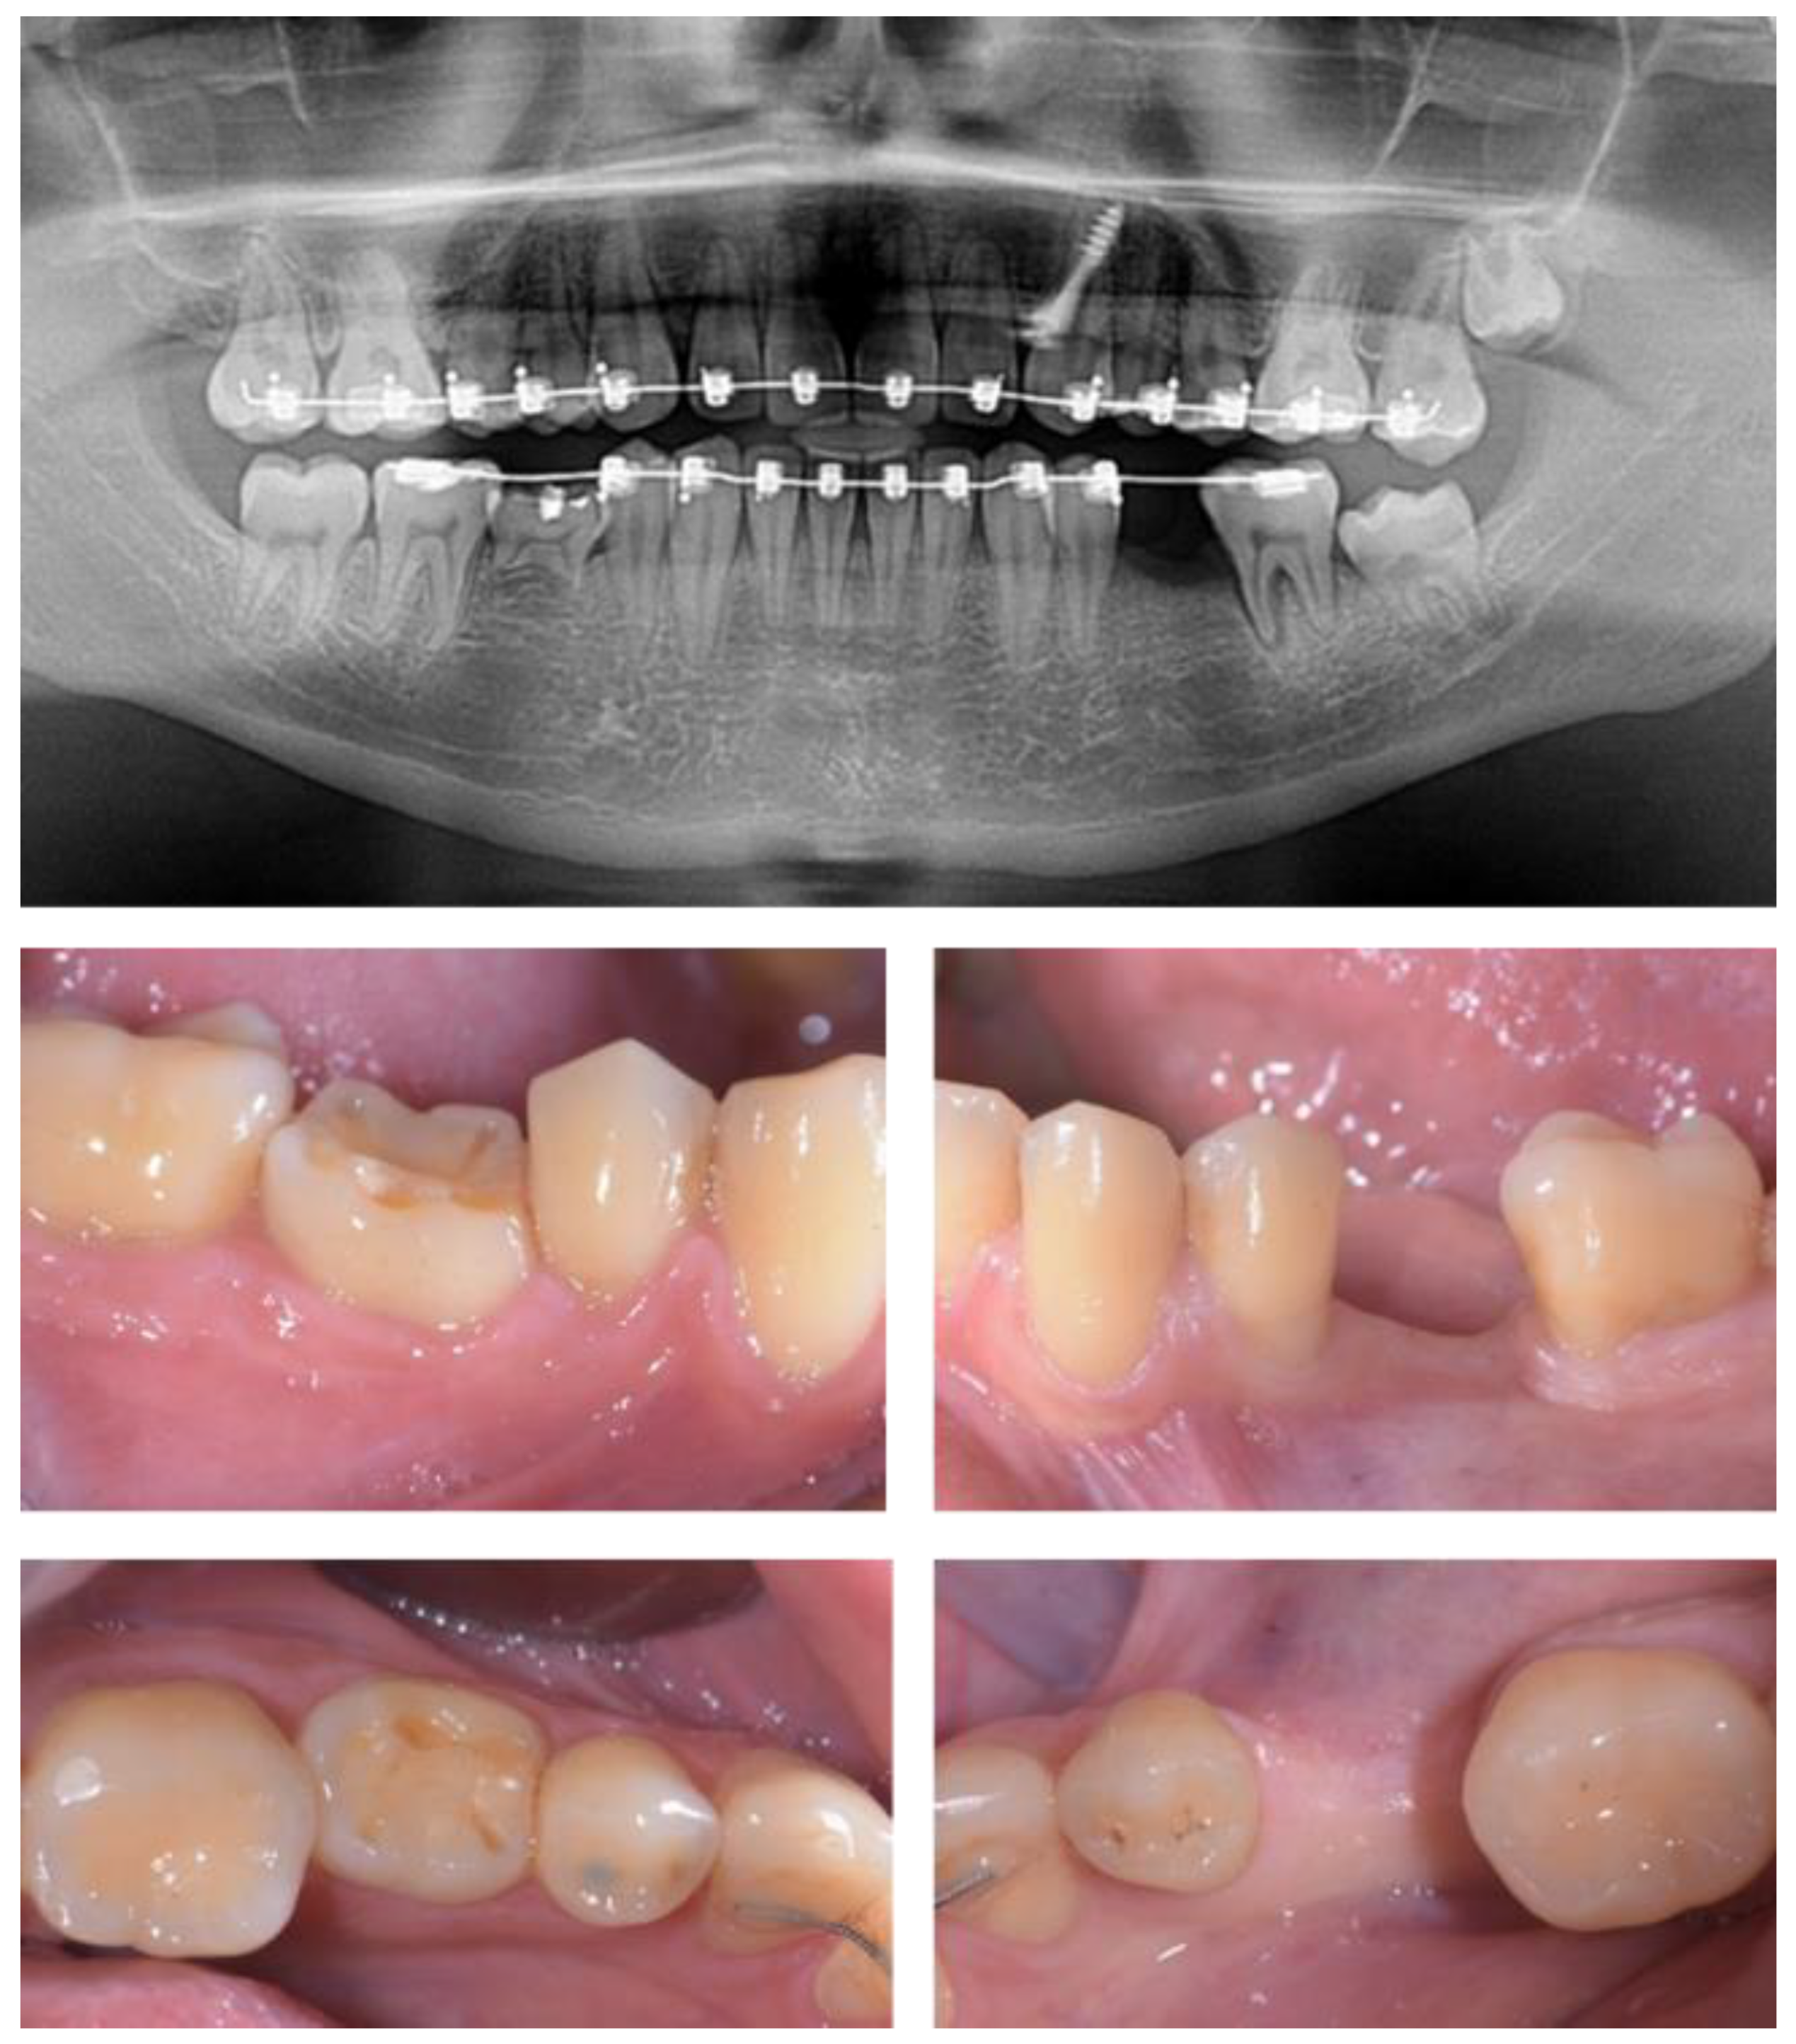

2.5. Individual Cases Description

- Case 1: